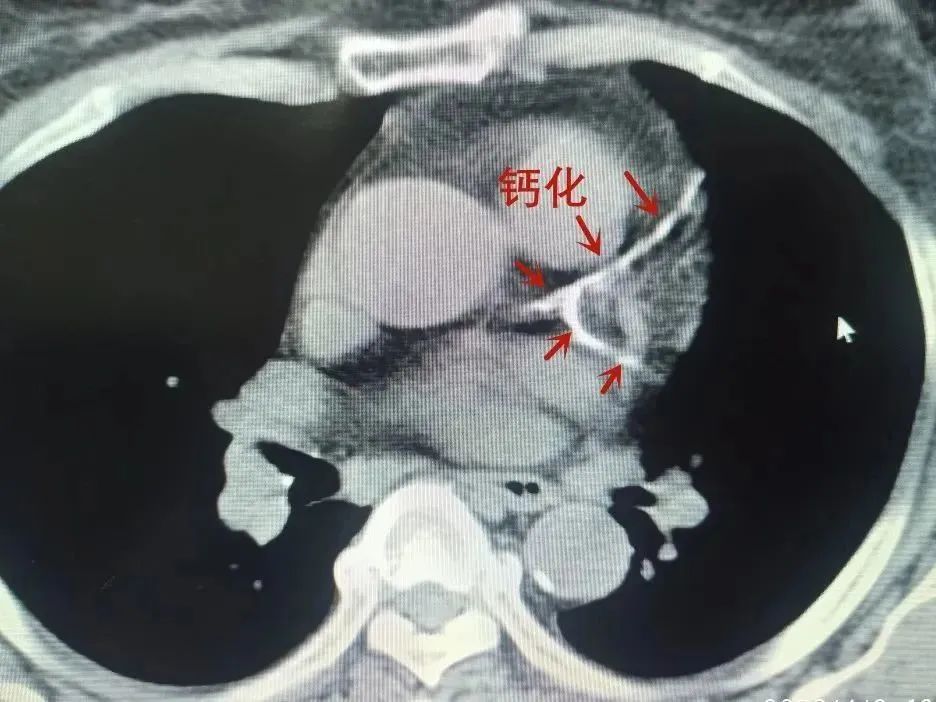

林大姐想:這可不是什么好征兆!于是她走進(jìn)了正興醫(yī)院心血管內(nèi)科,一查竟是冠狀動脈粥樣硬化性心臟病(簡稱冠心病)在作怪,胸部CT顯示,她的主動脈及冠狀動脈,已出現(xiàn)重度鈣化。

完善各項術(shù)前準(zhǔn)備,一場緊鑼密鼓的“護(hù)心”保衛(wèi)戰(zhàn)正式打響!正興醫(yī)院副院長、心血管內(nèi)科主任桑學(xué)東與其帶領(lǐng)的手術(shù)團(tuán)隊成員曾丁鄰醫(yī)師(主刀)、查慶春醫(yī)師配合默契,于患者右側(cè)橈動脈穿刺置管、送入導(dǎo)絲、送導(dǎo)管......一系列操作后,順利完成左右冠脈造影,造影結(jié)果顯示:

左主干遠(yuǎn)段真性分叉病變、伴重度鈣化、狹窄70-80%,累及前降支開口狹窄90-95%、回旋支開口狹窄30%;

前降支近段彌漫性病變伴鈣化、狹窄80%;回旋支近段彌漫性病變、狹窄20%;

右冠脈近段至中段全程彌漫性病變伴鈣化,近段狹窄50%、中段狹窄30%。

△ 治療前